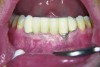

The presence of keratinized tissue around teeth and implants and its role in periodontal maintenance is somewhat controversial. It has been suggested that 2 mm of keratinized tissue is important to maintain gingival health around teeth.16 Minimal recession also facilitates maintenance by the therapist and plaque control by the patient (Figure 4 and Figure 5). Keratinized tissue around implants is also important. Chung et al17 completed a retrospective study examining the barrier function of keratinized tissue around dental implants. They examined 339 endosseous dental implants in place for at least 3 years in 69 patients and found that when an adequate band of keratinized tissue was present, less inflammation and plaque accumulation occurred (Figure 6 and Figure 7). Although there was no correlation to bone loss, there was improved comfort while cleaning the sites with keratinized tissue versus those areas that lacked keratinized tissue.

Fig 4. Severe recession visible on teeth Nos. 29 and 30.

Figure 4

Fig 5. Teeth Nos. 29 and 30 following connective tissue grafting showing minimal recession and improved tissue health.

Figure 5